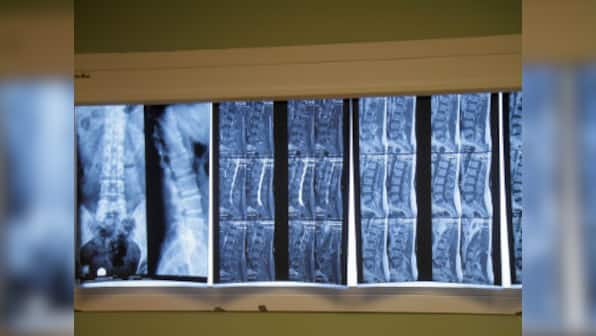

We’ve all heard horror stories about the guy in the gym who lifted incredible amounts of weight till one day he slipped a disc. Or about that one colleague who smoked incessantly and herniated a disc one fine day, just walking her dog. Slipped disc or disc herniation is an incredibly common and painful condition that affects the spine. [caption id=“attachment_7504341” align=“alignleft” width=“380”]  Representational image. Image source: Getty Images[/caption] On World Spine Day today (16 October), here’s everything you need to know about the spine and why spinal discs sometimes come out of alignment.